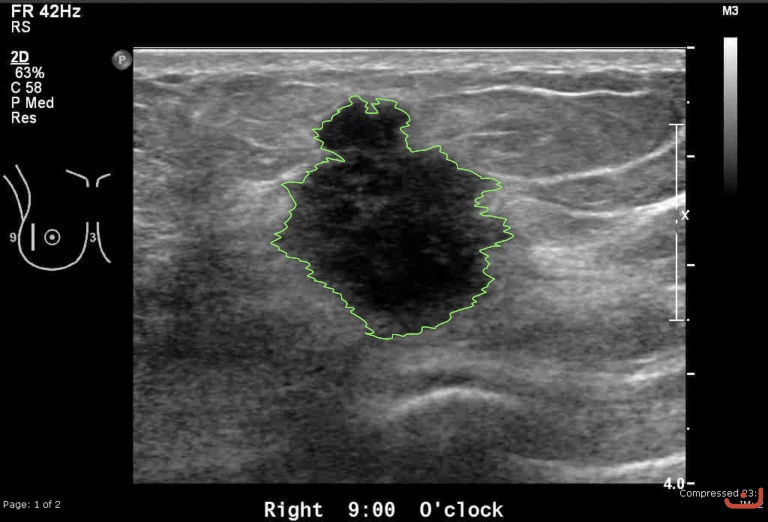

Case 22-G1

Malignant solid mass

Friday, 22 May 2015

191.76 KB (768 x 522 px)